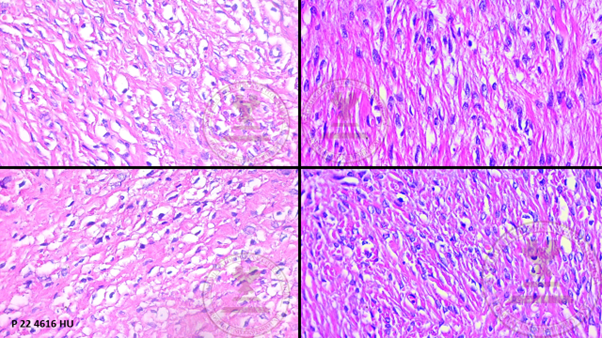

Histological images

1. Macroscopic description: adnexal tumor and right salpingus weighing 395g, with a smooth whitish surface alternating with rough areas and congestive vessels on its surface.

1. Macroscopic description: On section, the cut surface is solid, light brown in color with a swirled appearance with confluent whitish septa.

1. Panoramic view of the ovary showing the ovarian capsule, proliferation of bundles of spindle cells surrounded by a collagenous stroma accompanied by medium-caliber vessels. (HYE, 4x).

1. Proliferation of bundles of spindle cells surrounded by a collagenous stroma (H&E 10x).

1. Spindle-shaped cells with ovoid nuclei with pointed ends and scant eosinophilic cytoplasm with the presence of lipid inclusions that mixes with the surrounding eosinophilic stroma (HYE 40x).